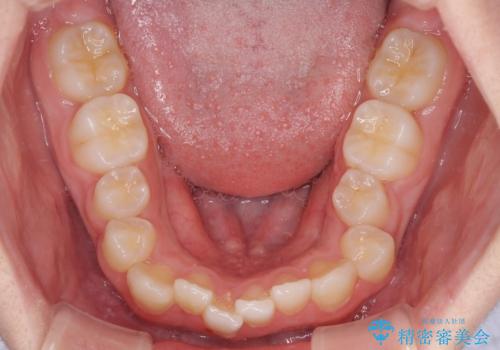

中学生のワイヤー矯正 クロスバイトを短期間で改善

- 前歯のクロスバイトを気にして来院された患者様です。

中学生であることから、治療期間を短縮できると判断し、ワイヤー矯正にて短期間で治療を行うこととしました。

叢生のため磨き残しの多い歯列でしたが、1年弱で治療を終了でき、磨き残しや歯肉の腫れが著しく改善されました。